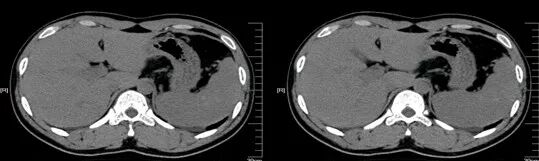

脾挫裂伤

病因病理

脾挫裂伤主要是指腹部受到外在力量的撞击而产生的闭合性损伤,是常见的腹部严重创伤,多由高处坠落、交通意外等引起。

临床表现

患者可有患部疼痛,但严重者多以失血性休克、腹部膨隆为首发症状。